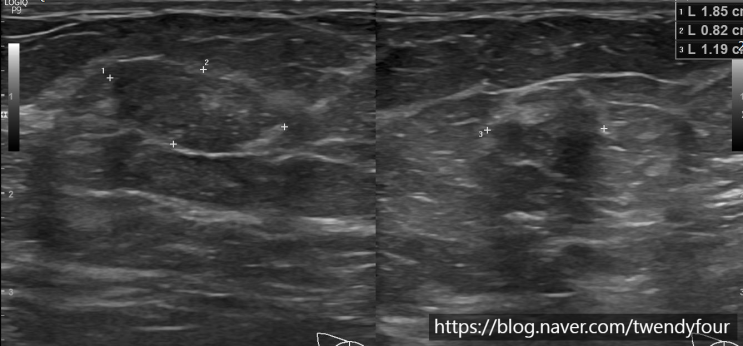

굿노트 스티커북 사용법 간단해요 (+스티커북 무료 공유) 안녕하세요 트웬디포입니다 :) 새해맞이 굿노트 ...

출처

https://blog.naver.com/twendyfour/222642878220